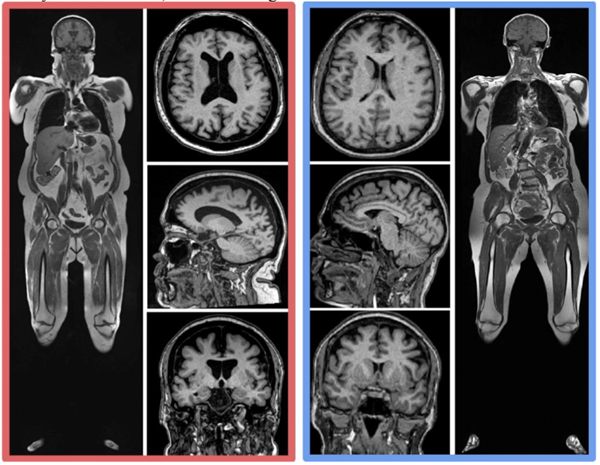

The results from this large data set were contextualized down to individual examples when comparing two MRI scans in two participants from the study with the same age and sex: